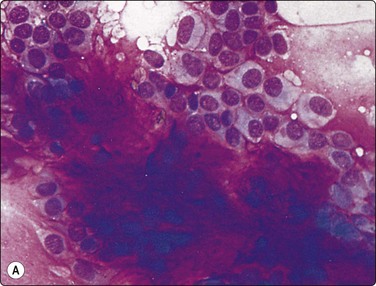

image

Fig. 4.24 Cystic salivary gland neoplasms

(A) Cystic Warthin’s tumor (macro); (B) Cyst fluid from same lesion with a single small group of bland oncocytic epithelial cells (Pap, IP); (C) Predominantly cystic pleomorphic adenoma (tissue section, H&E); (D) Cystic mucoepidermoid carcinoma with small tumor nodules in the cyst wall (tissue section, H&E). The fluids aspirated from (C) and (D) were practically acellular.

Cystic neoplasm is the most important differential diagnosis of non-neoplastic salivary gland cyst. The majority of cysts occurring in the major salivary glands are, in fact, associated with neoplasms, which may be benign or malignant. Warthin’s tumor and low-grade mucoepidermoid carcinoma are the commonest, but pleomorphic adenoma, cystadenoma, acinic cell carcinoma and other tumors may also be predominantly or partly cystic (Fig. 4.24). Aspirated fluid from a cystic neoplasm is often poor in cells and indistinguishable from fluid from a non-neoplastic cyst. If the lesion disappears completely after evacuation of the fluid, it is most likely of non-neoplastic nature. However, any remaining solid part must be biopsied. US guidance is helpful in this situation, particularly because the cyst may refill with blood following the initial FNB, rendering the solid portion impalpable. Clinical follow-up of cystic salivary gland lesions is essential if a specific diagnosis cannot be made.